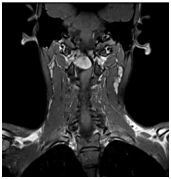

Rheumatoid arthritis atlanto-axiális közös.